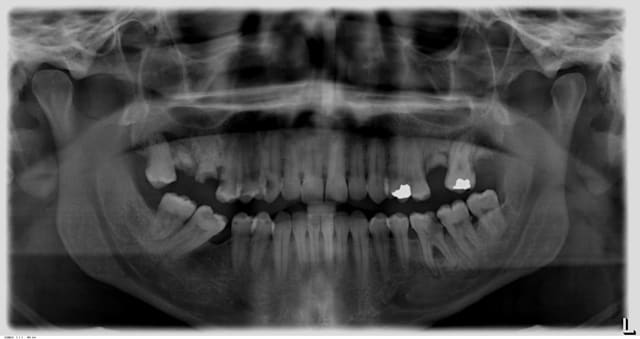

patient vu avec abcès-cellulite sur 36 avec atteinte furcation

1e scéance -> incision et drainage et nettoyage canalaire

2e scéance -> dent asymptomatique, pas de perf de la chambre visible, 3 canaux préparés,plus de saignement ou d'écoulement.

obturation par condensation latérale, radio contrôle et surprise!!!

Vu l'état de la bouche (cf pano) extraction.

"pas de perf visible" mais pourtant il y en a bien une et tu l'as obturée en pensant que c'était un canal mésial.